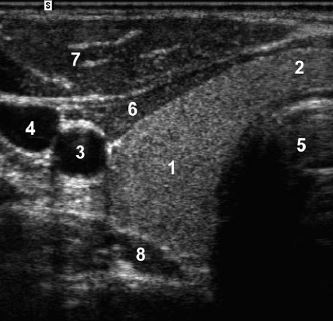

A

1. left lobe of liver

2. pancreas

3. porto-splenic confluence

4. aorta

5. IVC

6. SMA

7. CBD

8. gastroduodenal artery

The CBD travels in the most posterior aspect of the

pancreas. In fact, it often appears immediately anterior

to the IVC. The gastroduodenal artery arises from the

common hepatic artery and descends along the anterior

aspect of the head of the pancreas. These two structures

often appear as two small anechoic dots on transverse

views of the pancreatic head.